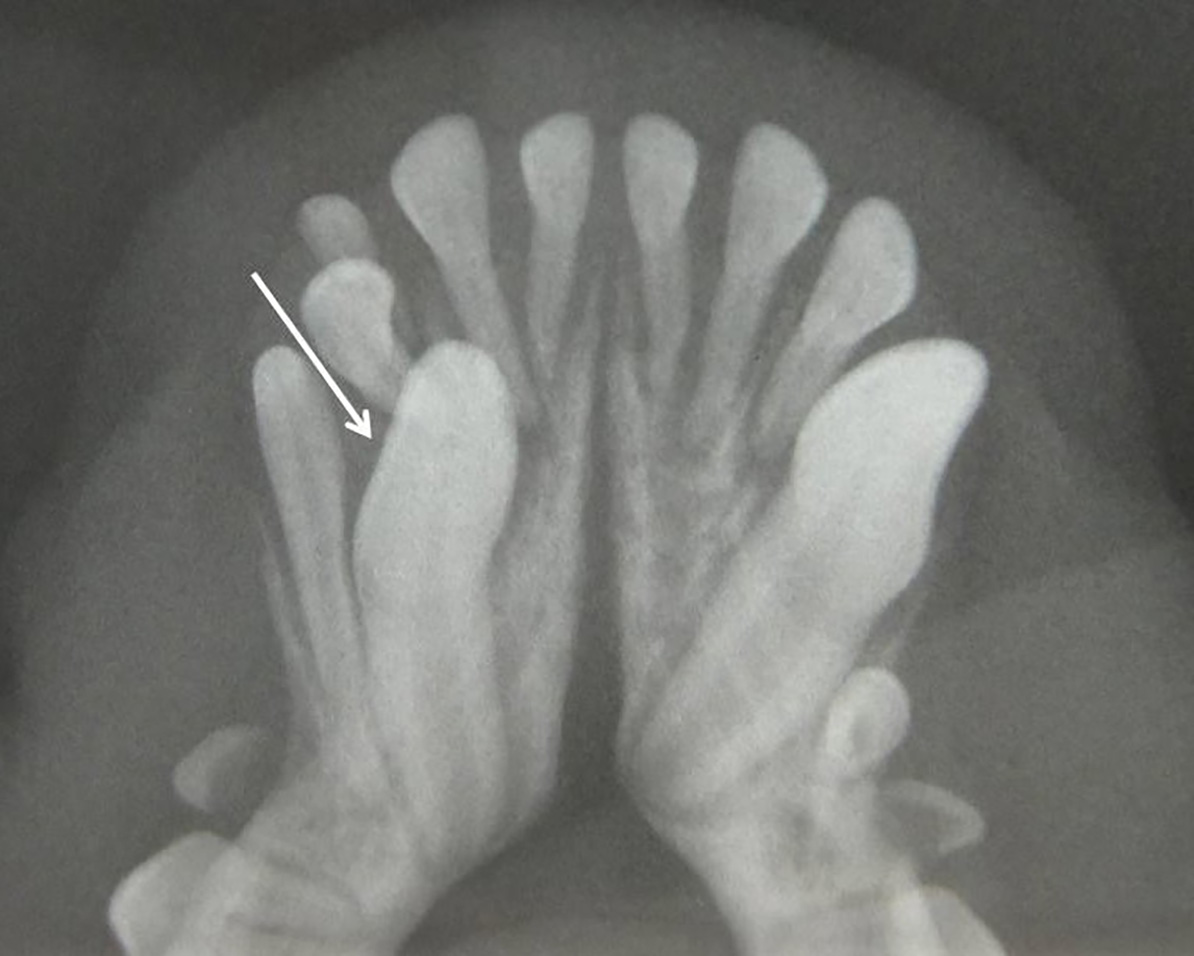

También puede ser debida a la pérdida dental (por EP, por ejemplo) o a fracturas de corona en las que quedan restos de estructuras dentales bajo la encía. Por tanto, dependiendo de ello, decidiremos el enfoque terapéutico que tomaremos en cada paciente con ausencia dental. (imágenes 14-17).

Aumento del número de dientes

La presencia de dientes supernumerarios también debe ser estudiada mediante la radiología intraoral. La causa principal es genética y la radiología nos permitirá valorar su naturaleza, si se trata de un diente definitivo o la falta de exfoliación de dientes deciduos (en caso de no tenerlo claro a la inspección visual). En este último caso, podremos valorar el estado de la raíz y su relación con el diente permanente, aspectos que debemos tener en cuenta a la hora de realizar su extracción (imágenes 18 y 19).

Las consecuencias pueden ser insignificantes en zonas de mínima intercuspidación, pero pueden ser causa de lesiones traumáticas o apiñamiento que disminuyan los mecanismos fisiológicos de autolimpieza.